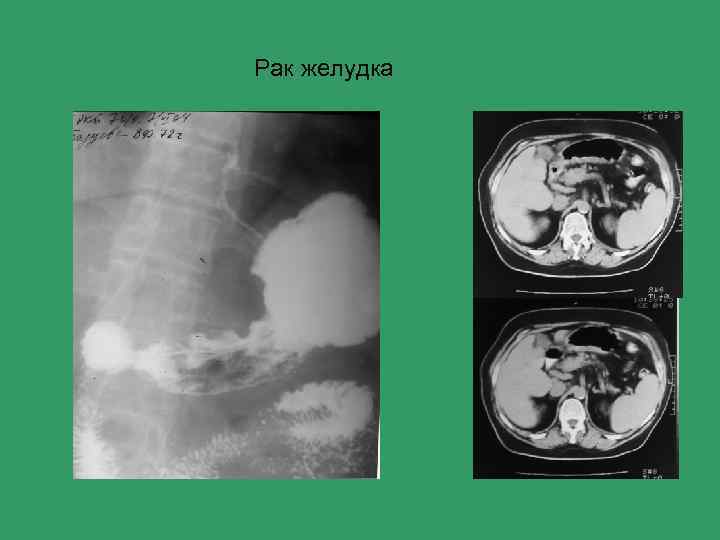

Рак желудка